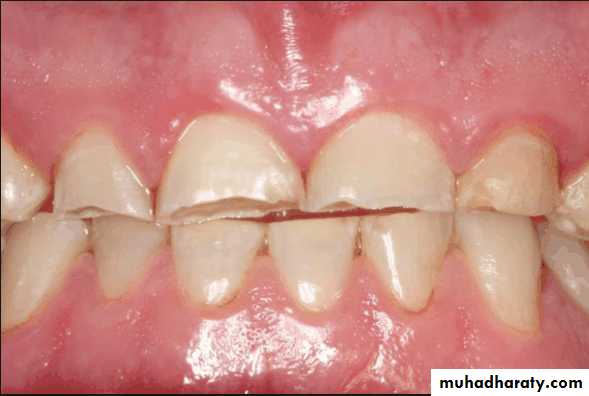

• Evaluated to determine their effect on prognosis

• Bruxism and clenching:• Bruxism is often initiated by interceptive occlusal contacts

• The occlusion should be analyzed to determine any correction is indicated, if the efforts are unsuccessful the patient should wear occlusal splint to protect the remaining teeth.